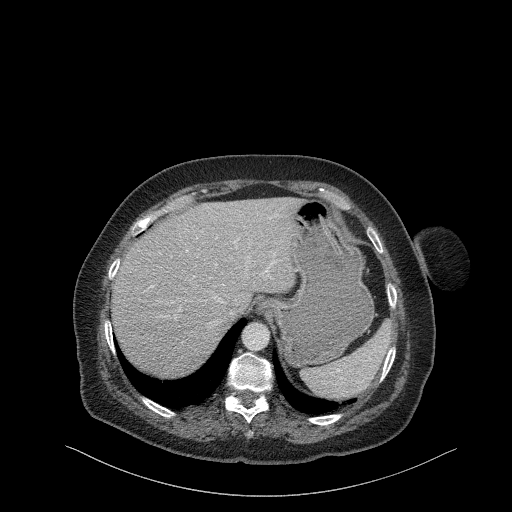

Original VENOUS CT scan

Full window (WL 1023.5, WW 4095 β†’ Low βˆ’1024, High +3071)

Actual HU range: [-160.0, 240.0]

Lung window (WL -600, WW 1500 β†’ Low βˆ’1350, High +150)

Actual HU range: [-160.0, 150.0]

Mediastinum window (WL 40, WW 400 β†’ Low βˆ’160, High +240)